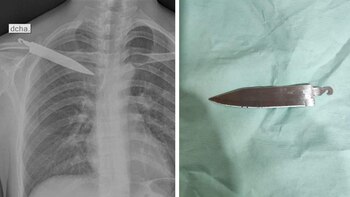

Había sufrido un robo hace un mes y le apareció un fuerte dolor en la espalda que día a día se fue incrementando hasta que no soportó más y fue llevado por sus familiares a un hospital en Junín. En el hombro de Gerson Tarazona Gálvez, un joven de 28 años, los médicos encontraron el pedazo de un cuchillo incrustado en uno de sus hombros.

Según comentó el joven, hace un mes había sufrido un asalto en la ciudad de Huánuco, y en su intento de defenderse le clavaron un cuchillo por la espalda. Aquella vez fue trasladado al hospital de la zona donde solo le cosieron la herida, pero no se dieron cuenta del cuchillo clavado en su interior.

Tiempo después, Tarazona Gálvez viajó al distrito de Pangoa, y al ver que ya no podía mover el brazo, fue llevado al hospital San Martín de Pangoa II. Ahí fue sometido a una intervención para extraerle el objeto punzocortante.

Además señalaron que el médico de guardia lo evaluó y ordenó que se le pasara rayos X. Cuando observaron la placa quedaron sorprendidos, un objeto punzocortante se encontraba alojado en su espalda. Por ello, ordenaron que fuera intervenido quirúrgicamente para extraerle el cuchillo y salvarle la vida.

“La caja torácica tiene medios de protección, en este caso, el hueso omóplato y otros que han impedido que se dañe el pulmón y el corazón. (El cuchillo) ha estado ubicado solo en la pared torácica, en los músculos”, explicó uno de los médicos que intervino.